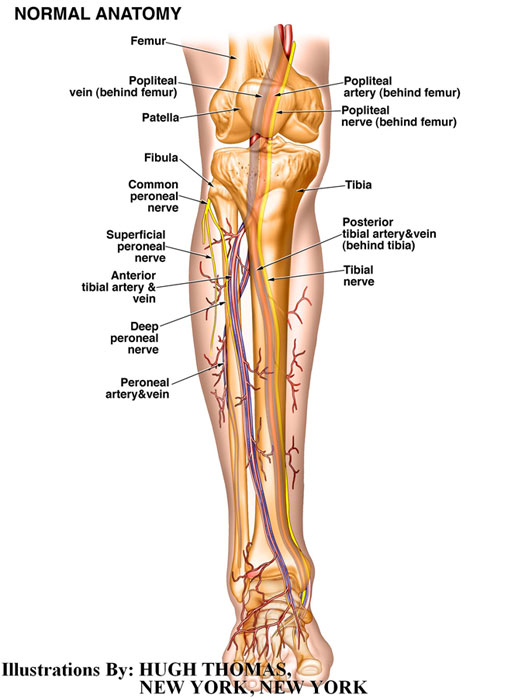

The medical illustrations on this page are examples of the details the attorneys at the Law Offices of William Cafaro prepare for jury presentations.